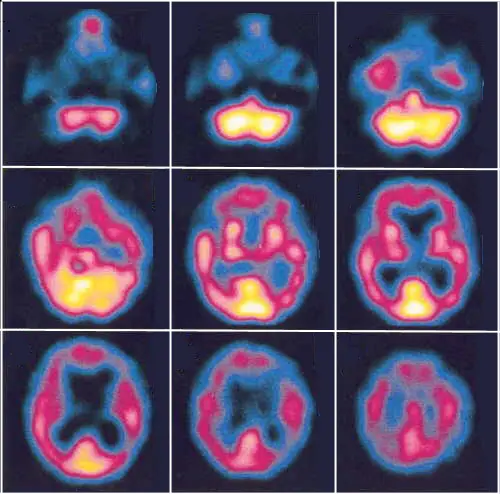

En la PET el defecto funcional cortical es mayor que en la enfermedad de Alzheimer y se extiende selectivamente hacia las regiones posteriores en el área visual primaria y áreas asociativas temporales, parietales y occipitales.